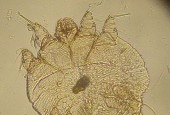

Świerzbowiec ludzki

Sarcoptes scabiei

Rodzina należąca do rzędu Astigmata, podgromady roztocze (Acari), gromady pajęczaki (Arachnida), podtypu szczękoczułkowce (Chelicerata) oraz do typu stawonogi (Arthropoda).